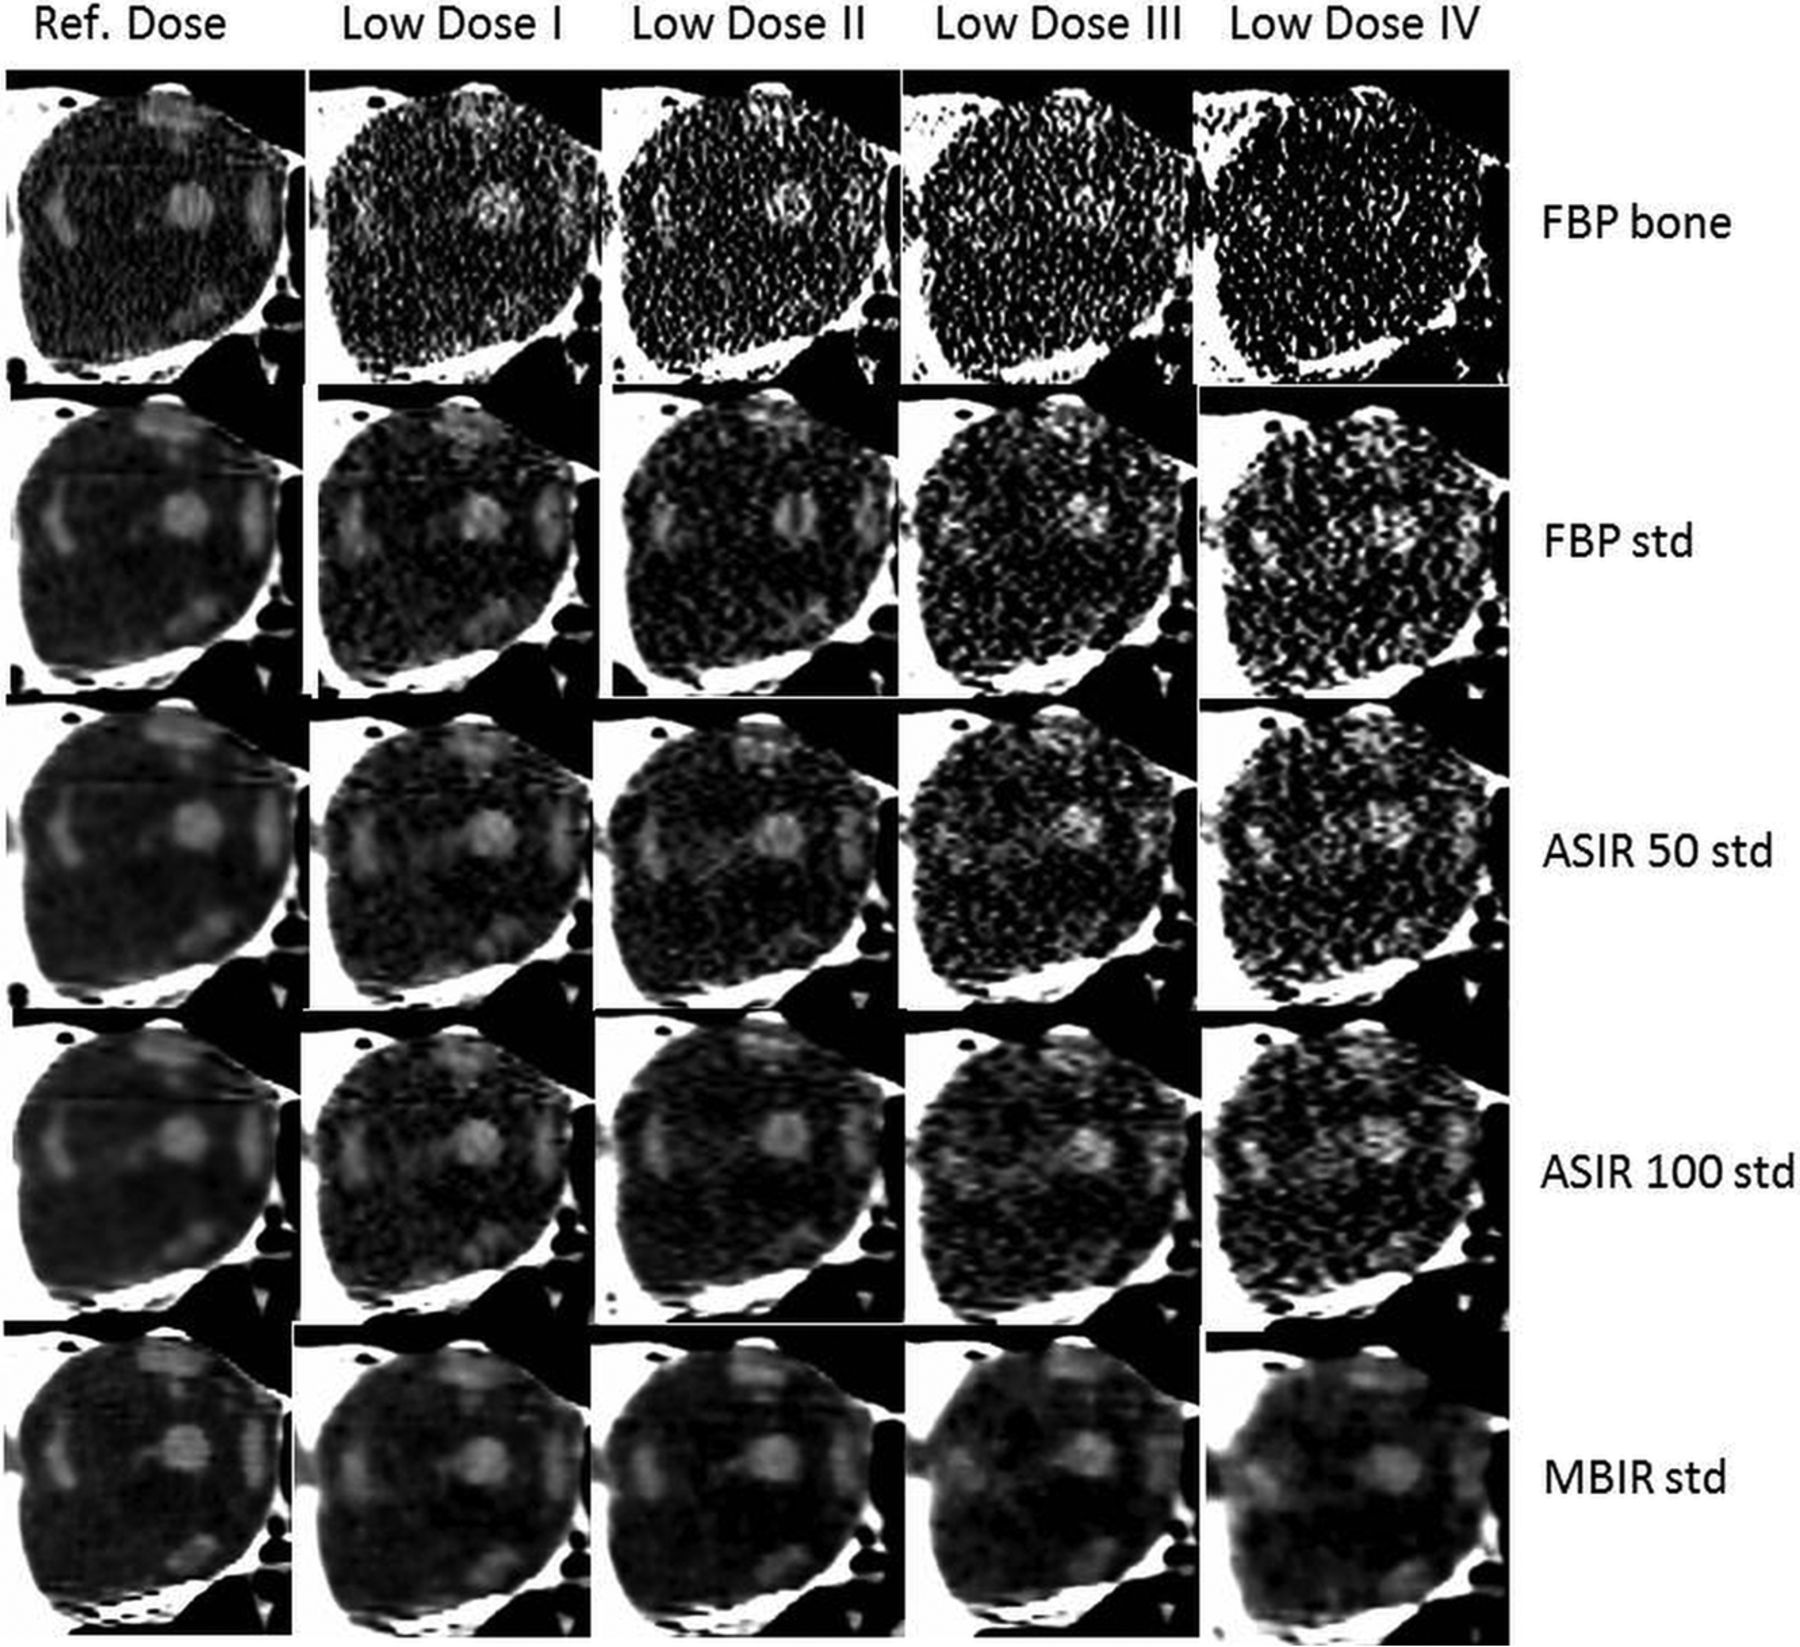

Figure 1 shows images including the reference dose protocol with FBP using the bone and standard kernels, and all low-dose protocols with FBP, ASIR-50, ASIR-100, and MBIR with the standard kernel. The mean CNR and SDs of the ON and IRM for each protocol and reconstruction technique can be found in Table 2.

Images of the right orbit with different protocols (vertical columns), reconstructions, and kernels (horizontal columns). Std indicates standard.

Compared with the reference dose protocol with FBP bone, which was given the reference score of 3 (average = equal to reference), scores decreased progressively during dose reduction (see Table 2 and the comparison of the images in Fig 1). Images with a standard kernel showed a higher score than with the bone kernel. The reference dose protocol with FBP standard showed a score of 4. In LDP-II, the standard kernel could retain a score of 2 (suboptimal but sufficient) in contrast to the bone kernel, which was insufficient. ASIR-50 had no remarkable effect over FBP on subjective scores. ASIR-100 showed a small effect. MBIR showed the best subjective score in all images. MBIR obtained a score of 4 for LDP I and II and retained a score of 2 for LDP III and IV. ON showed better subjective visibility then IRM.